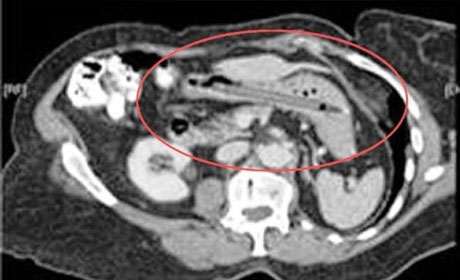

Mədəsindən əl bombası çıxdı - ŞOK FOTOLAR

İnsan nələri udmağa qadir deyil? Yaxud mədədən nələr gəlib-keçmir? ANN.Az-in oxuculara təqdim etdiyi fotolar bir daha insanın nələrə qadir olduğunu göstərir. 1. İlan balığı2. Qaşıq3. Batareyalar4. Canlı qurbağa5. Mismar6. Dərmanlar 7. Nişan üzüyü8. Qayçı9. Tük yumağı10. Mobil telefom11. Qələm12. Yay13. Əl bombası14. Açar15. Lampa